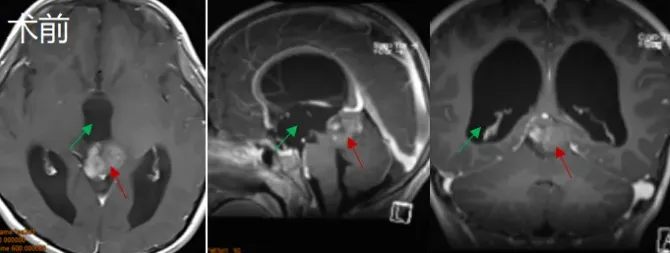

一次看似平常的摔跤,对活泼好动的孩子来说本是常事。但对于6岁的鑫鑫而言,一次意外摔破头皮后的检查,却揭开了更严峻的真相他的大脑中心,松果体区,潜藏着一个不断长大的肿瘤。 临...

Tank!病房中,一位6岁男孩的欢呼预示着生命的重启。这是他开颅术后的第二天,而这一天,全家人足足等了2年。 01 意外发现的松果体区占位 Pineal region tumor 2021年,6岁男孩鑫鑫因意外摔伤头皮...

六岁的鑫鑫,因在幼儿园意外摔伤头皮就诊,CT检查意外捕捉到松果体区阴影与局部钙化灶;进一步MRI精查,一枚221417mm的占位病变随之浮出水面。 三十六岁的晴晴,不过是因鼻炎顺带行颅脑...